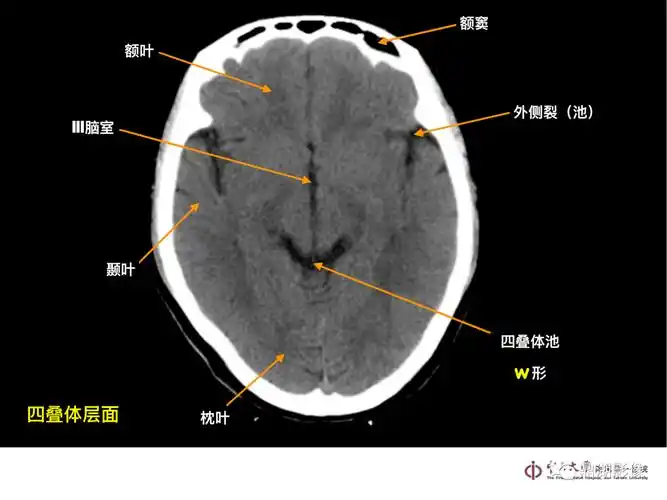

头部ct影像解剖